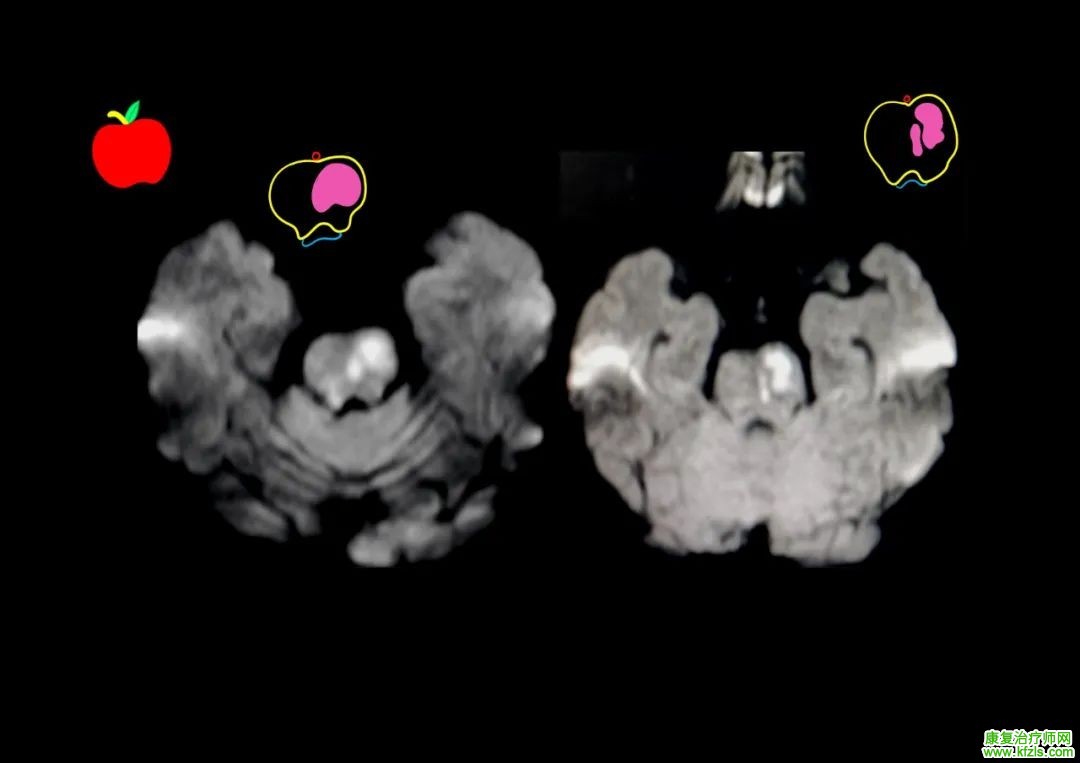

临床病例

病例 1:58 岁男性,「高血压」、「糖尿病」病史,急性共济失调起病,后出现眩晕、中枢性眼震、左侧面部及右下肢针刺痛觉减退、Horner 征、饮水呛咳、声音嘶哑、咽反射减弱,核磁如下:

脑干梗死

图源:参考文献 / 徐桂兴手绘

病例 2:33 岁男性,眩晕、恶心呕吐,查体见眼震,声音嘶哑、饮水呛咳,查体:软腭上抬无力,咽反射消失,左侧偏身痛觉减退,小脑性共济失调。

图源:参考文献